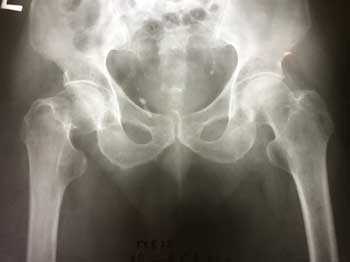

а. рентгенограмма тазобедренного сустава с переломом шейки бедра, б. рентгенограммы после остеосинтеза винтами.